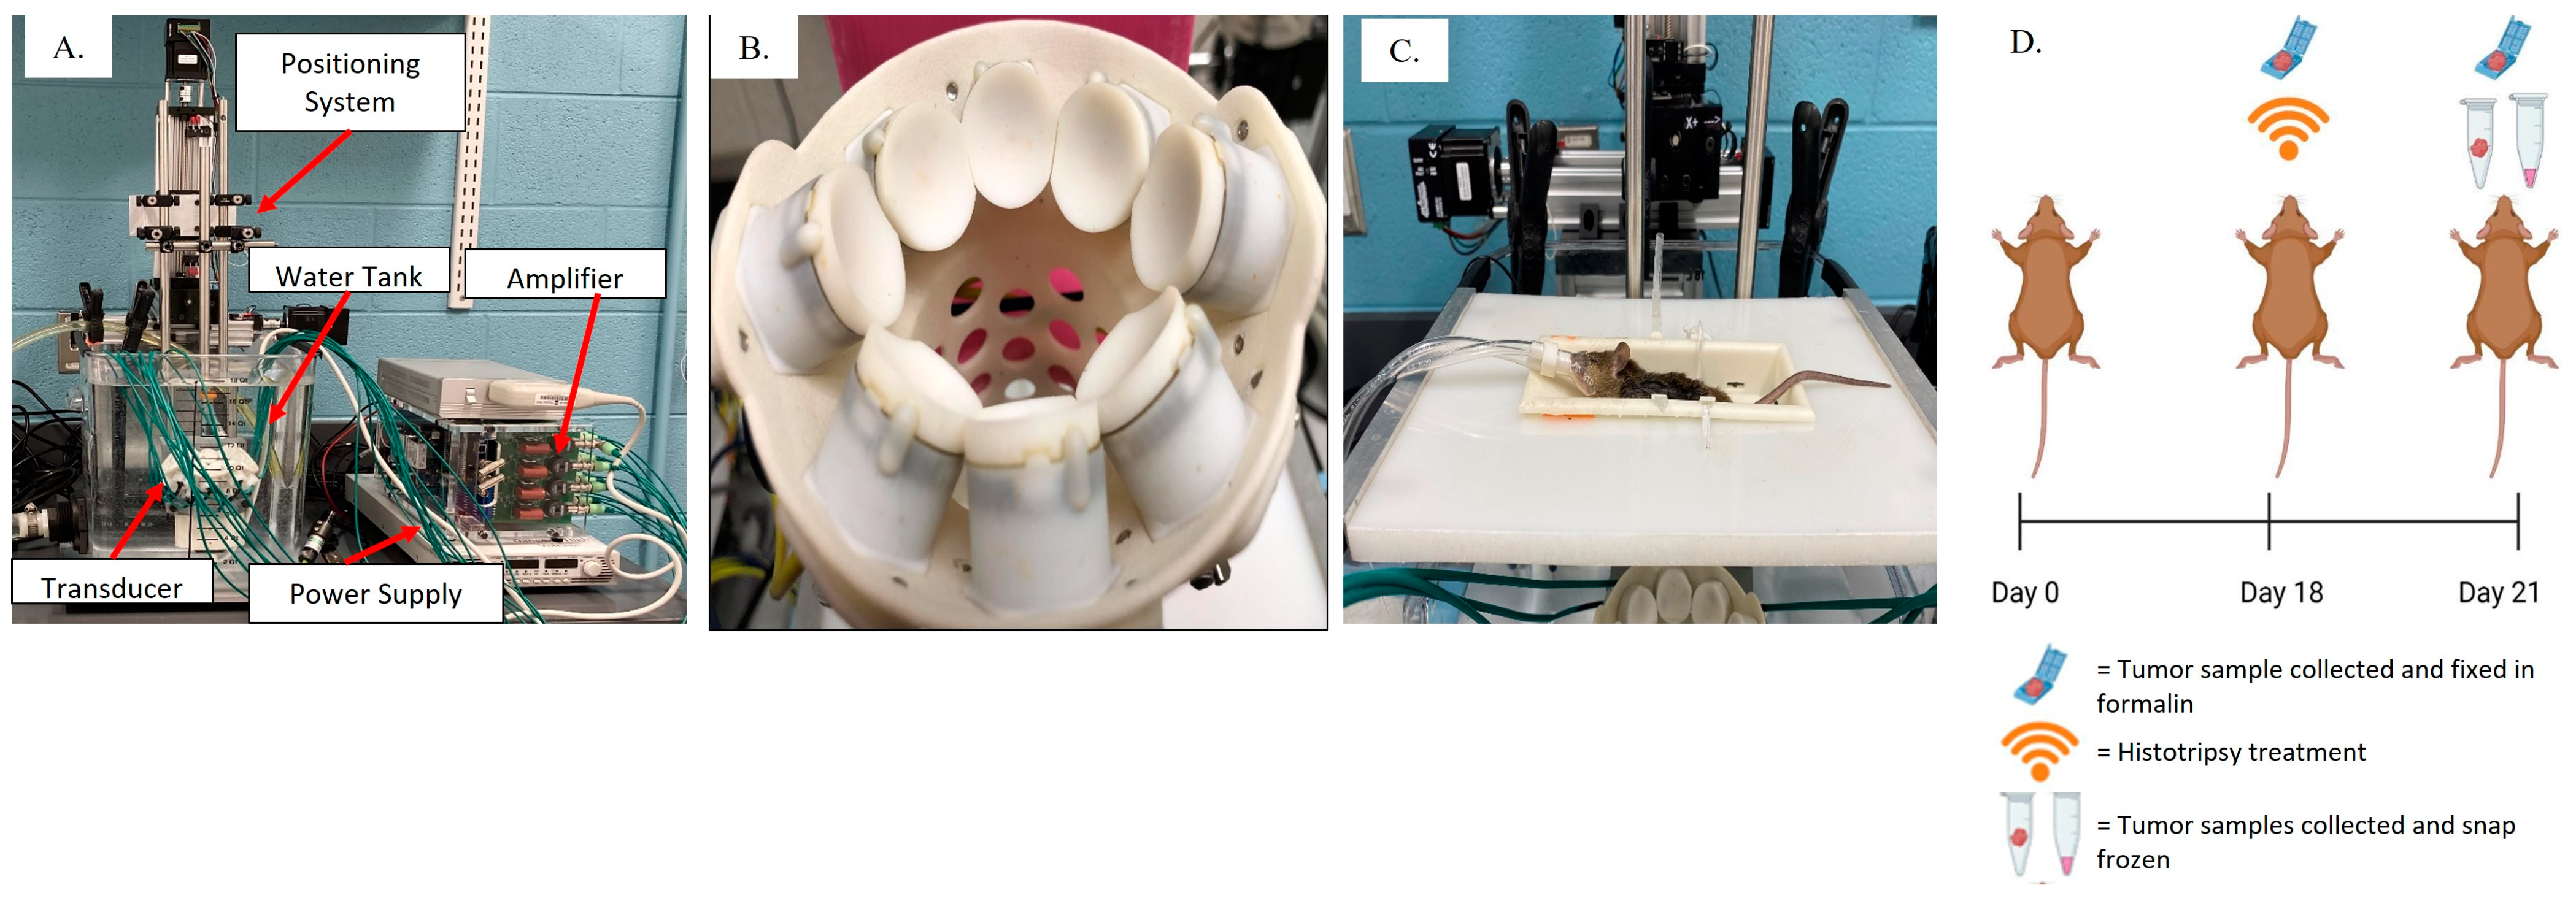

2.2. Histotripsy System and Ablation Parameters

3.1. Tumor Tissue Can Be Effectively and Precisely Targeted and Ablated with Histotripsy